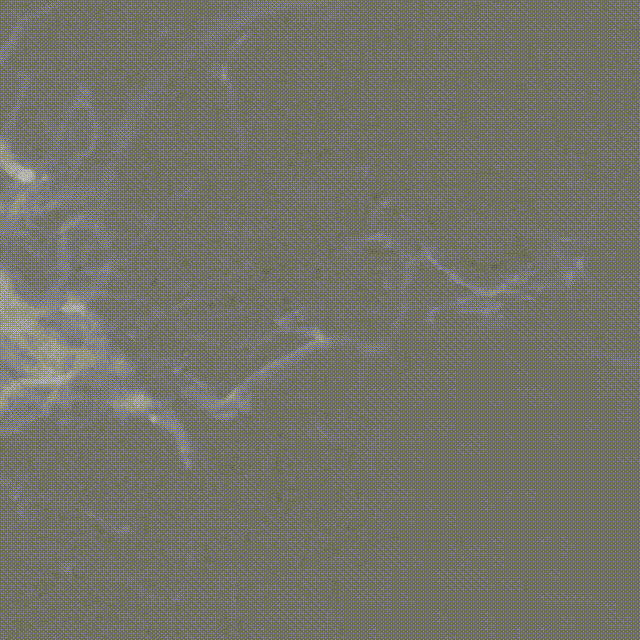

拔管后造影:

SONIC微导管头端解脱,右侧眼动脉显影良好,未见拔管牵拉痉挛表现

可见SONIC微导管可解脱头端显影